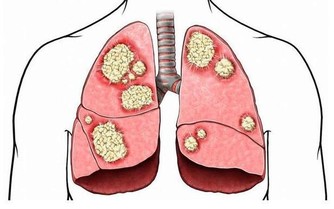

這是因為感冒時亂吃抗生素就會讓腎臟受損,可是如果拖著不去治療,看似不太嚴重的感冒、咽喉炎都會引發腎臟疾病。除了常見的呼吸道感染外,其他肺炎、肝炎等感染性疾病也會引發不同類型的腎病。